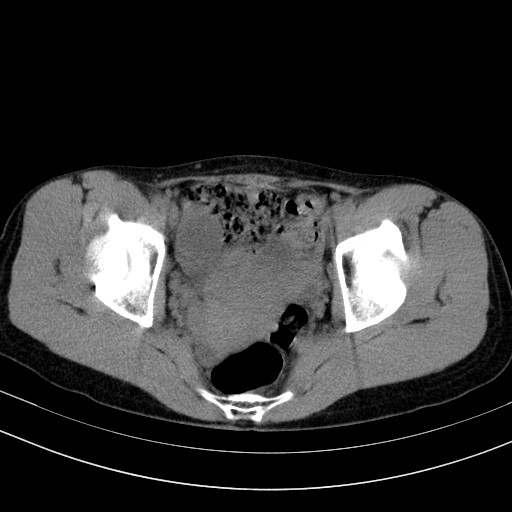

以下是引用随光逐影在2009-4-7 8:17:00的发言:[br]考虑宫颈占位性病变(宫颈癌?);建议行进一步检查。

以下是引用jiangjing在2009-4-7 16:46:00的发言:[br]宫颈增大,结构不清,右侧附件区可疑囊样占位,建议增强及mri 检查